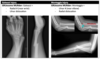

Colles vs Smith fracture

Colles fracture ## Footnote Typically FOOSH forwards Extra-articular radial # with dorsal (posterior / back of hand) angulation and displacement

Smith Fracture ## Footnote Typically FOOSH back of hand Extra-articular radial # with volar (anterior / palmar) angulation and displacement

**Colles - ‘dinner fork type deformity’** Features of the injury 1. Transverse fracture of the radius 2. 1 inch proximal to the radio-carpal joint 3. Dorsal displacement and angulation of the distal radius

**Smith's fracture (reverse Colles' fracture)** 1. Volar angulation of distal radius fragment (Garden spade deformity) 2. Caused by falling backwards onto the palm of an outstretched hand or falling with wrists flexed